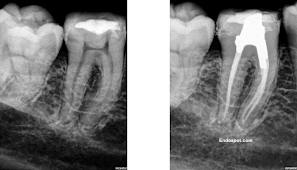

του οργανισμού-και από την οστεΐνη στη ρίζα. Κάτω από αυτούς τους ιστούς υπάρχει ένα άλλο σκληρό στρώμα ιστού, αλλά μαλακότερο από την αδαμαντίνη, η οδοντίνη. Στο κέντρο του δοντιού υπάρχει ένας θάλαμος που περιέχει αγγεία, νεύρα και λεμφαγγεία που τρέφουν το δόντι και ονομάζεται πολφός. Οι ριζικοί σωλήνες είναι πολύ μικρά και λεπτά χωρίσματα, τα οποία ξεκινούν να διακλαδώνονται από το πάνω μέρος του πολφού μέχρι την άκρη της ρίζας.

Ένα δόντι έχει τουλάχιστον ένα, και συνήθως, όχι περισσότερους από τέσσερις ριζικούς σωλήνες.

Η ενδοδοντική θεραπεία, γνωστή ως απονεύρωση, αφορά το εσωτερικό του δοντιού και συνίσταται στην αφαίρεση των μαλακών ιστών από τον πολφό (στο κέντρο του δοντιού) και από τους ριζικούς σωλήνες (στις ρίζες), καθαρισμό και απολύμανση και την αντικατάστασή τους με ένα κατάλληλο εμφρακτικό υλικό.